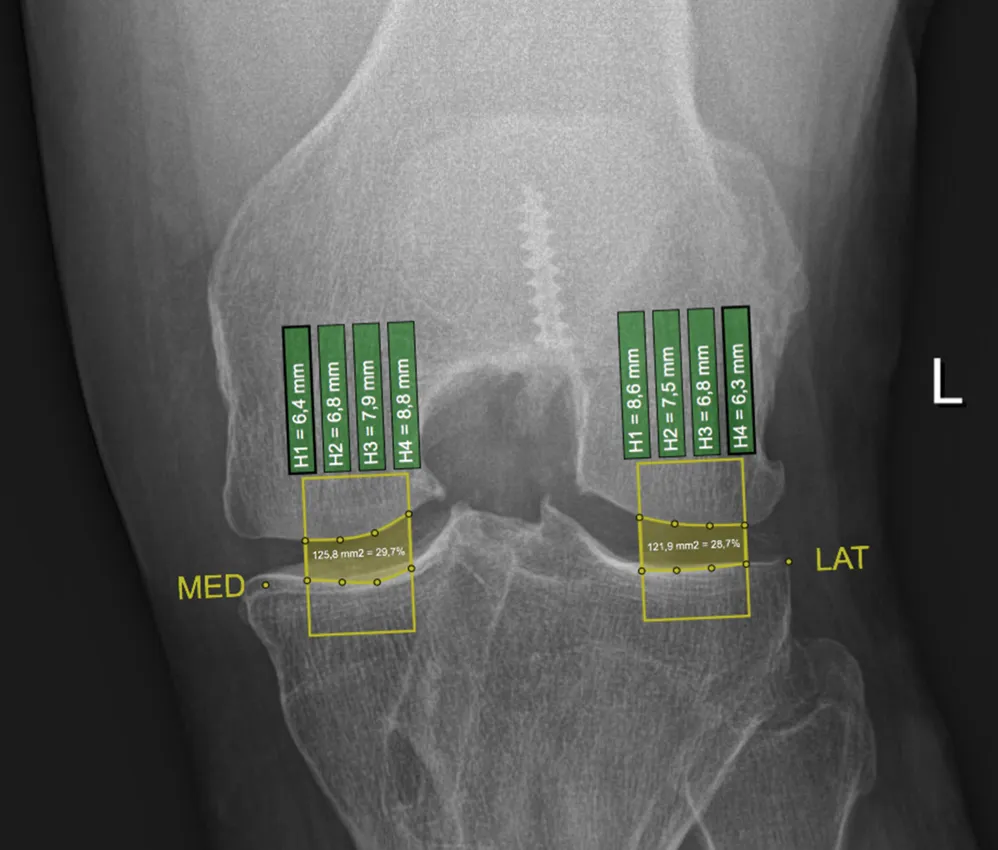

Developed an interactive clinical visualization system at ImageBiopsy Lab for analyzing osteoarthritis progression in knee joints. The platform integrated machine-learning models for automated landmark detection and quantitative measurement extraction from radiographic images, enabling structured visualization of joint-space narrowing and anatomical changes over time. The system translated computational imaging models into an accessible web-based analytical interface for research and clinical evaluation. The project formed the basis of my Bachelor’s thesis under the supervision of Prof. Eduard Gröller.